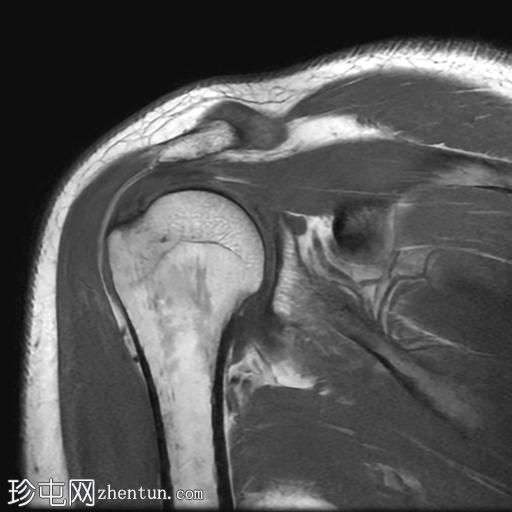

冠状位PD序列

脂肪抑制序列

冈上肌腱关节面中前部纤维可见部分撕裂(边缘撕裂),伴局部骨髓水肿。

冈上肌腱关键区纤维以及冈下肌腱均可见肌腱病。

肩锁关节周围可见轻度关节囊肥厚和退行性改变。

此外,肩峰下滑囊内可见积液。

MRI 检查结果符合冈上肌腱的典型边缘撕裂,也称为部分关节面肌腱撕脱。